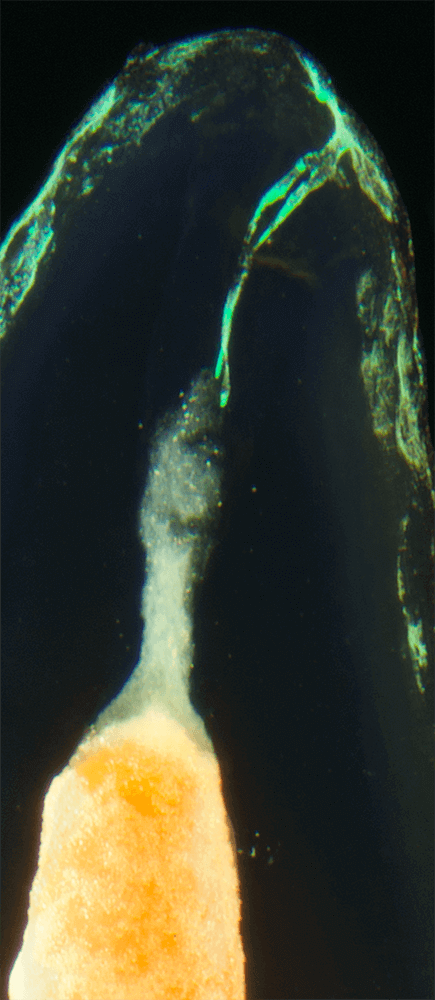

Das Verfahren, Zähne in durchsichtige Präparate zu überführen ist schon über 100 Jahre alt. Aber erst durch die Weiterentwicklung der alten Technik und die Kombination mit moderner Fotografie sowie der Entwicklung eines geeigneten Gefäßes zur Fotografie ist es meinem Vater Dr. Holm Reuver gelungen, einzigartige Bilder vom Inneren der Zähne aufzunehmen.

Die Bilder sind in verschiedenen Größen wählbar und auch als POPART-Variante erhältlich. Sie sind hervorragend geeignet für die Beratung von Patienten vor endodontischen Behandlungen, aber auch ein beliebter Eyecatcher im Wartezimmer. Außerdem haben die Bilder einen bedeutenden Stellenwert für die Erforschung der Pulpatopografie und für die Lehre im Bereich der Endodontie.

CLEARINGSERVICE bietet Ihnen die Möglichkeit, wurzelgefüllte Zähne mit der Technik des Transparentmachens untersuchen zu lassen. Das geht sehr einfach: Sie schicken uns den zu untersuchenden Zahn, dieser wird dann in ein transparentes Präparat überführt und mit hochwertiger Makrofotografie ausgewertet. Anschließend bekommen Sie die angefertigten Präparate zusammen mit der Fotodokumentation zugeschickt.